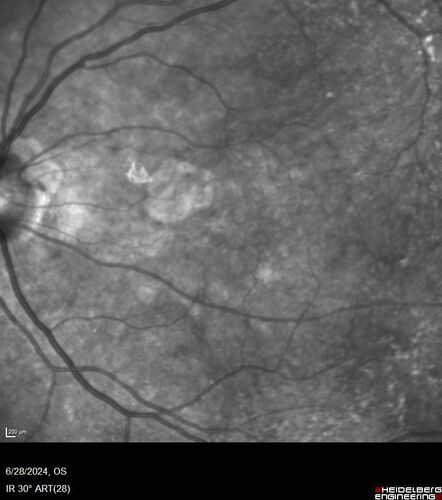

Elmiron (pentasosan polysulfate) Macular Toxicity

77 year old female who had been on Elmiron for 20 years and stopped it 2 years ago